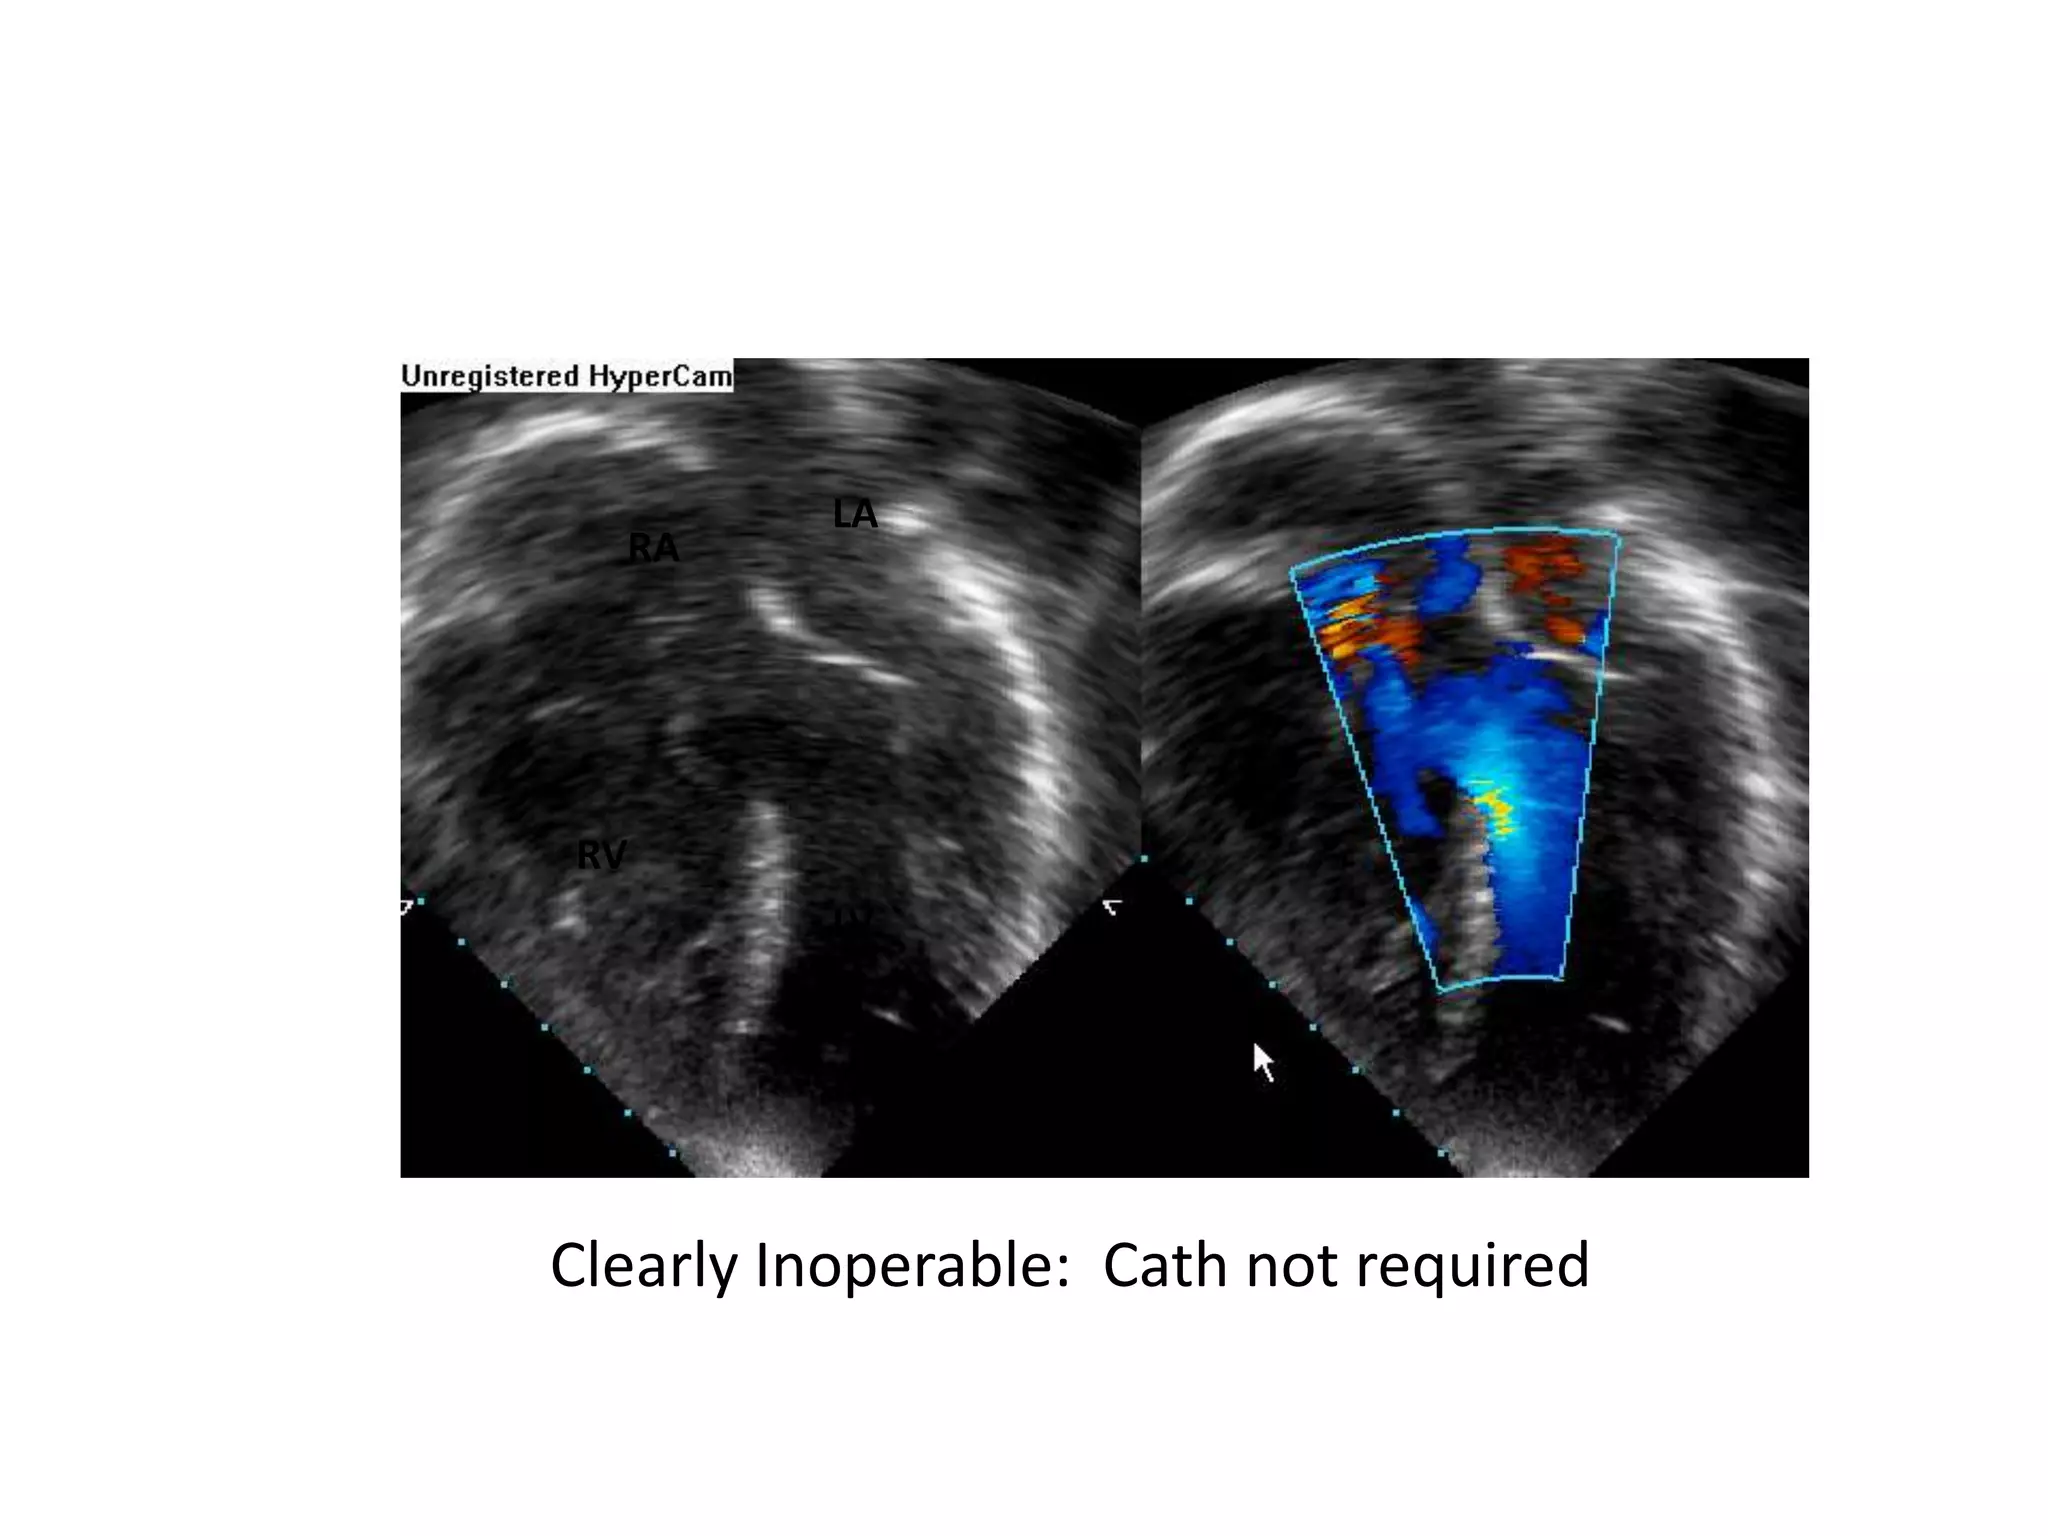

CLINICAL ASSESSMENT • Serialassessment by multiple experienced clinicians improves the reliability of clinical examination as a tool in determining operability • The presence of ‘clinical cyanosis’ or saturations <90% is a strong predictor of inoperability whereas the clear detection of a MDM on serial assessment strongly favours operability.

Clearly Inoperable: Cathnot required RV LV RA LA